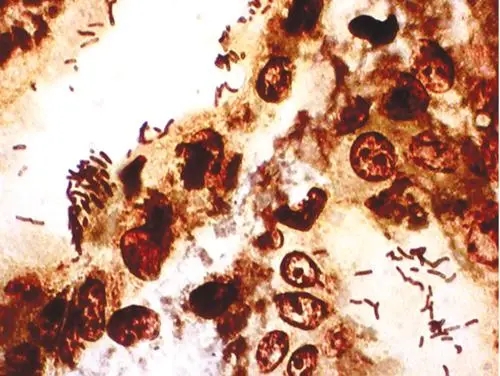

网状纤维染色,reticular fiber,是指在疏松结缔组织中含量较少,纤维较细,有分支,彼此交织成网状。

网状纤维染色,reticular fiber,是指在中含量较少,纤维较细,有分支,彼此交织成网状。